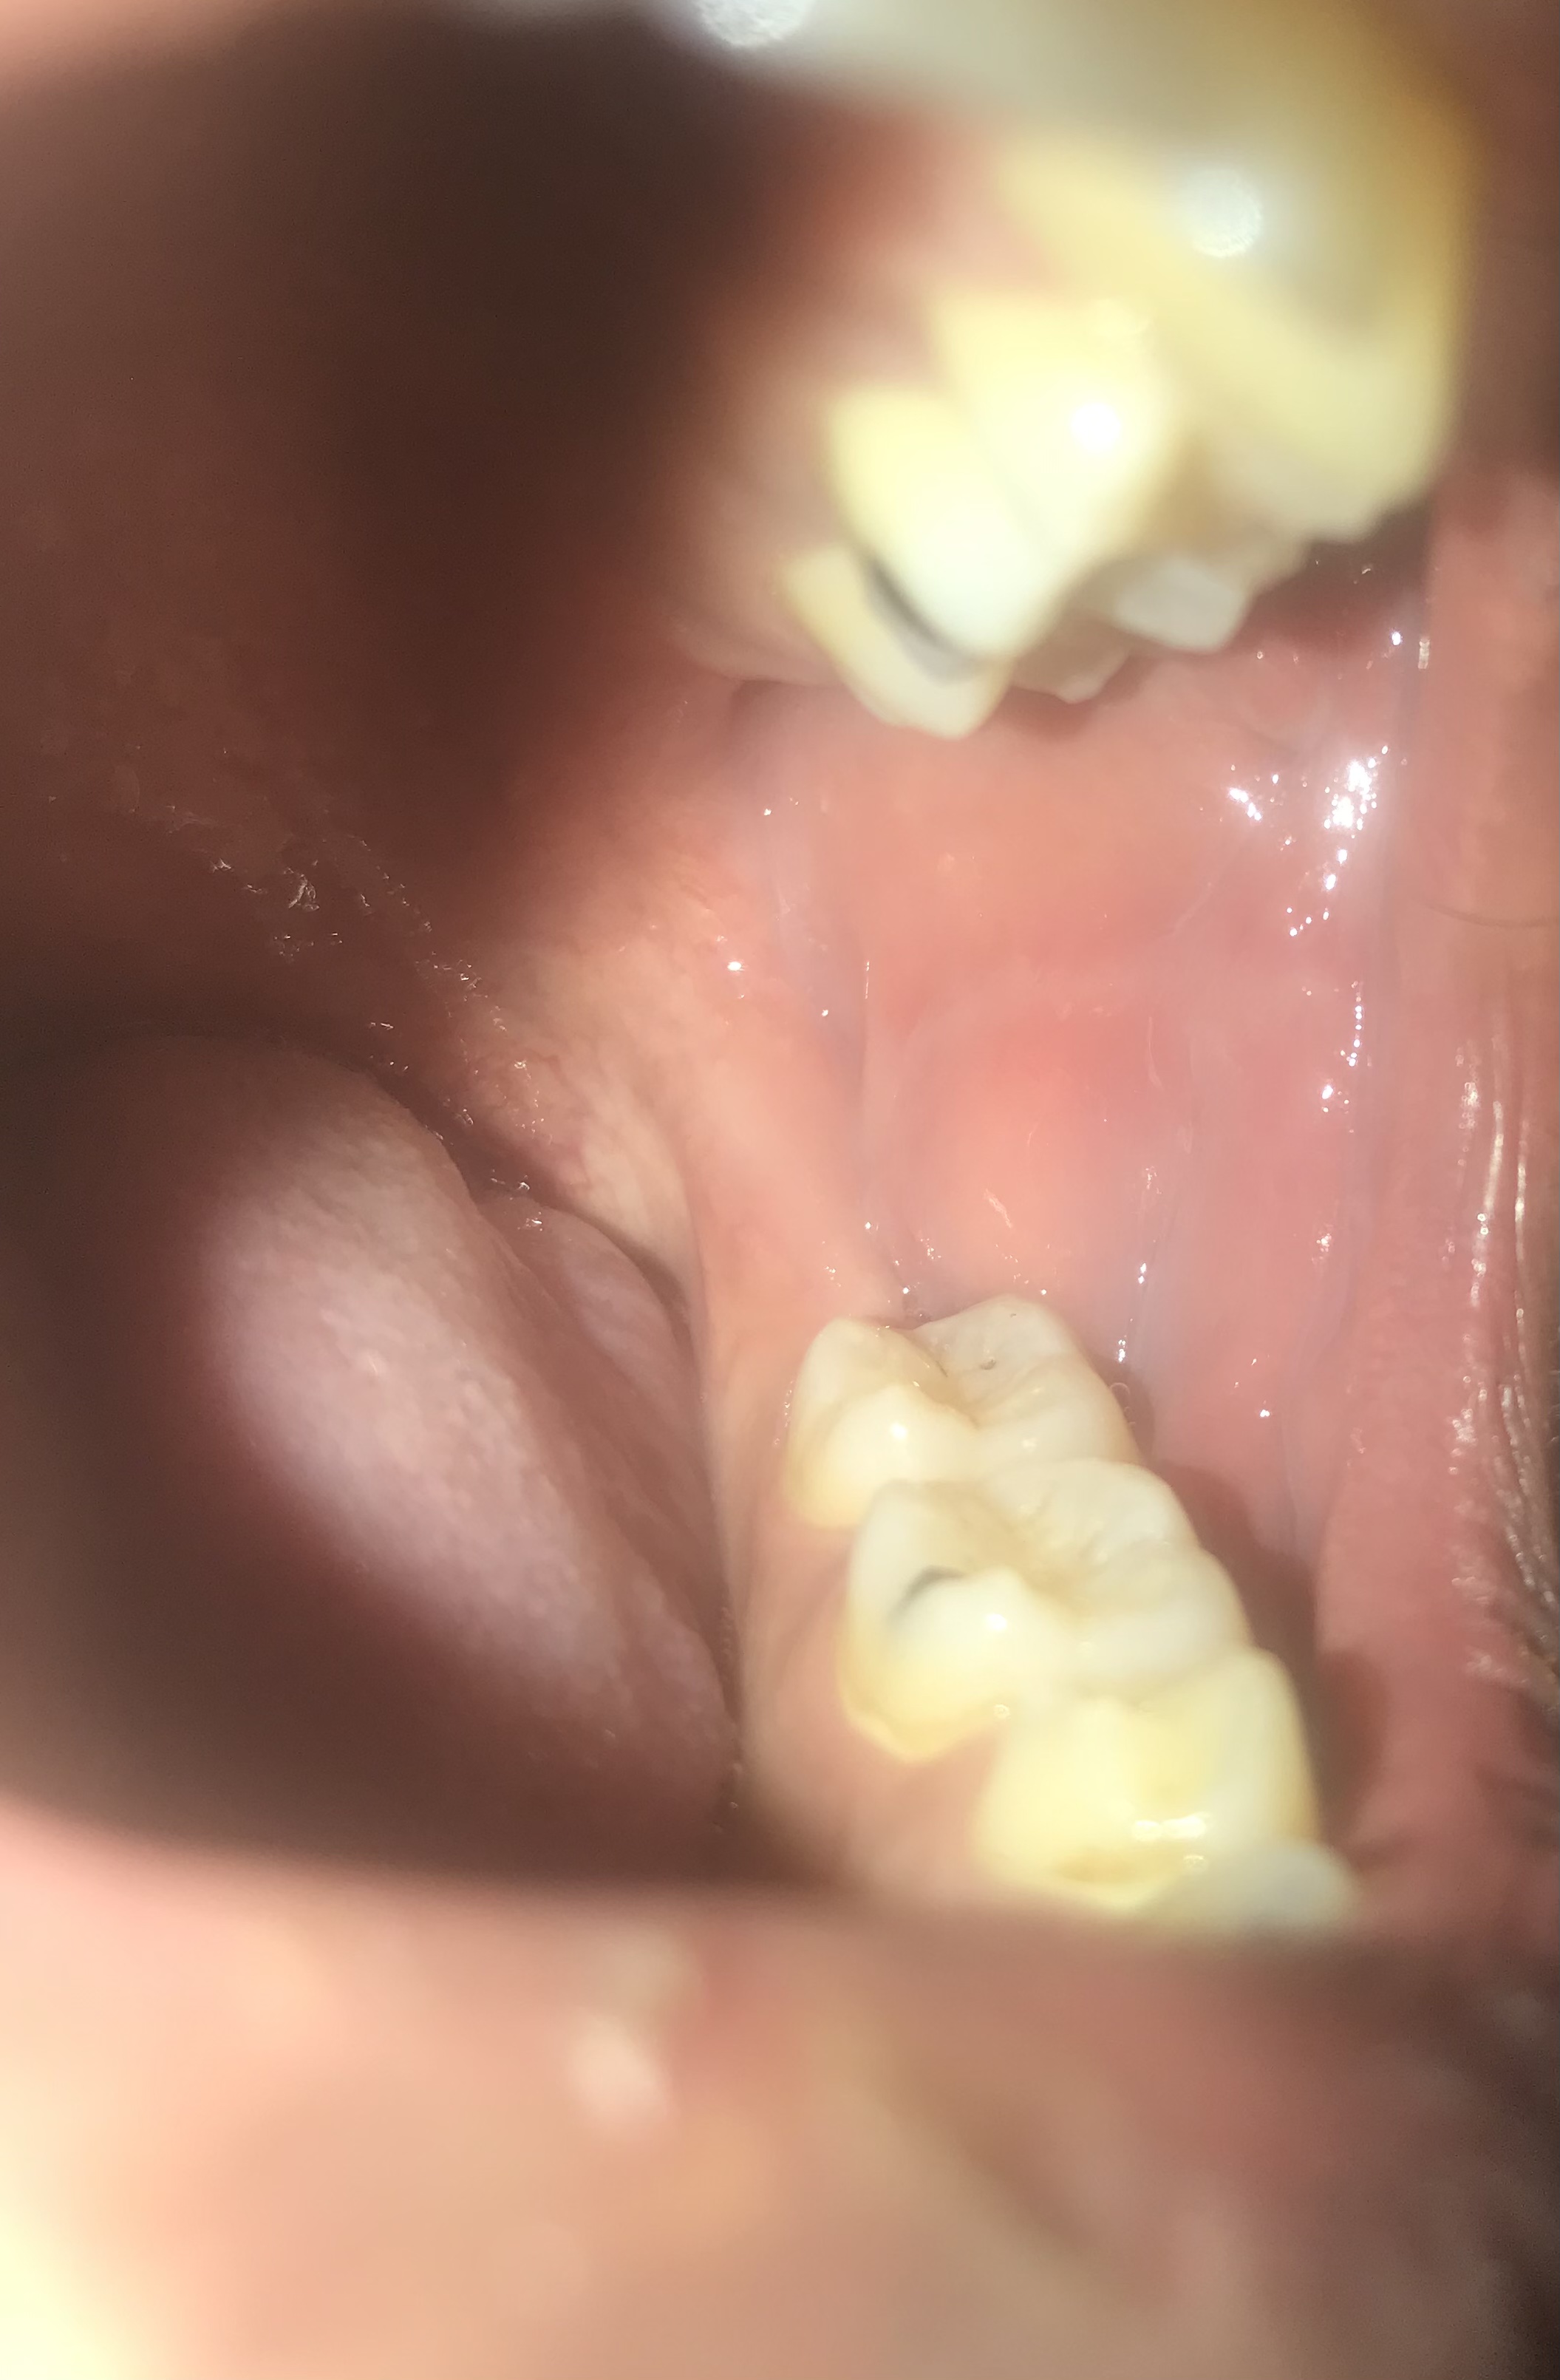

7 พฤศจิกายน 2568 13:45:22 #1 มีเส้นแบบนี้ในกระพุ้งแก้มทั้งสองข้างผิดปกติไหมคะ https://haamor.com/media/create_topic/20251107134032.jpeg

10 พฤศจิกายน 2568 10:40:14 #2 จากภาพที่ส่งมา ในกระพุ้งแก้ม ที่เห็นเป็นเส้นคล้ายเส้นเลื

ส่วนที่เห็นเป็นรอยย่น เป็นภาพของกระพุ้งแก้มปรกติ

แต่ถ้ามีการหนาตัวขึ้น ควรพบแพทย์เพื่อตรวจ เพราะแพทย์มีไฟส่องสว่าง จะเห็นได้ชัดครับ